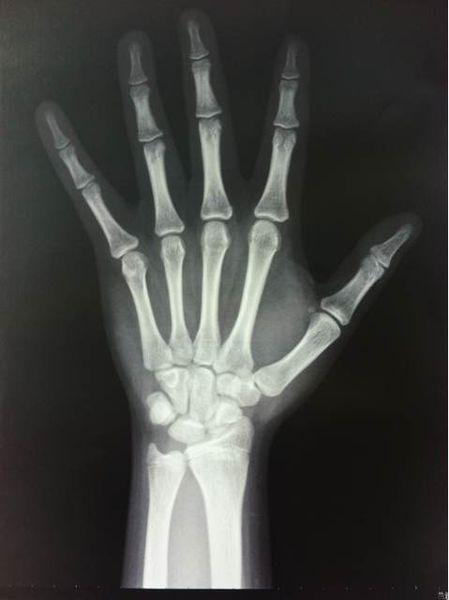

骨骺线是用于生长的软骨,它会随着我们的营养吸收,与内分泌激素的作用下不断的骨化。但是这一过程并非无休止的。它会随着年龄的增长而逐渐变短,当骨骺与干骺端的软骨完全骨化后,就形成一条紧密的缝,此时骨骺线完全闭合,我们就停止的人 体自然长高的过程。